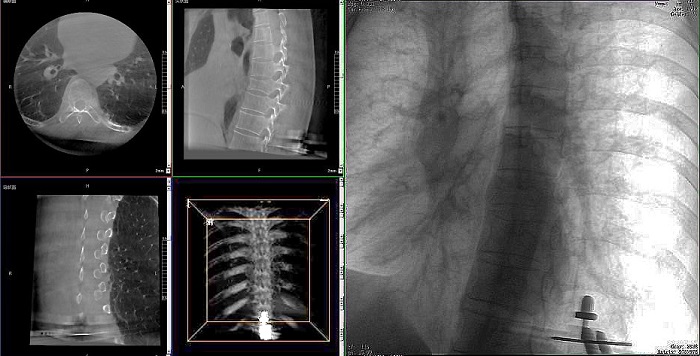

①機(jī)器人輔助胸椎手術(shù)操作難點(diǎn)之圖像采集

胸椎緊鄰肺部,患者的呼吸運(yùn)動會造成椎節(jié)的相對移動,獲取清晰、穩(wěn)定的影像較為困難。高質(zhì)量的影像是精準(zhǔn)導(dǎo)航的重要前提,胸椎手術(shù)中,如果呼吸造成的移動無法得到有效控制,則會降低導(dǎo)航的精度,增加手術(shù)風(fēng)險(xiǎn)。人體深吸氣胸圍與深呼氣胸圍的差值約為6~8厘米。

普愛醫(yī)療手術(shù)導(dǎo)航定位系統(tǒng)解決方案

高清三維成像:普愛醫(yī)療精研三維成像技術(shù)13年,自研的三維C形臂可為手術(shù)提供清晰、穩(wěn)定的三維圖像,為醫(yī)生精準(zhǔn)開展胸椎手術(shù)提供影像保障。

亞毫米級精度:普愛醫(yī)療三維C形臂+骨科手術(shù)機(jī)器人,基于同一技術(shù)平臺研發(fā),借助一體化自適應(yīng)配準(zhǔn)及無損圖像傳輸技術(shù),整體協(xié)同性更高,精度可達(dá)亞毫米級。

快速掃描:麻醉師通過適當(dāng)?shù)暮粑刂?,配合三維C形臂的快速掃描模式,可以在短時(shí)間內(nèi)完成圖像采集,減少因呼吸運(yùn)動造成的圖像干擾。